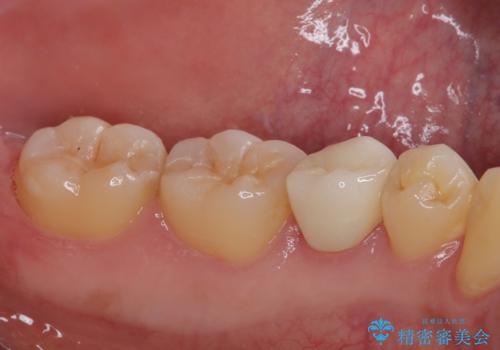

フロスがちぎれることもなくなり、被せものが入っていることを忘れていたと大変喜んでいただきました。適合の良い被せものは二次的な虫歯の再発リスクを低減してくれます。

今後の予定は患者様のタイミングで歯茎から少し見えている親知らず抜歯を行っていく予定です。